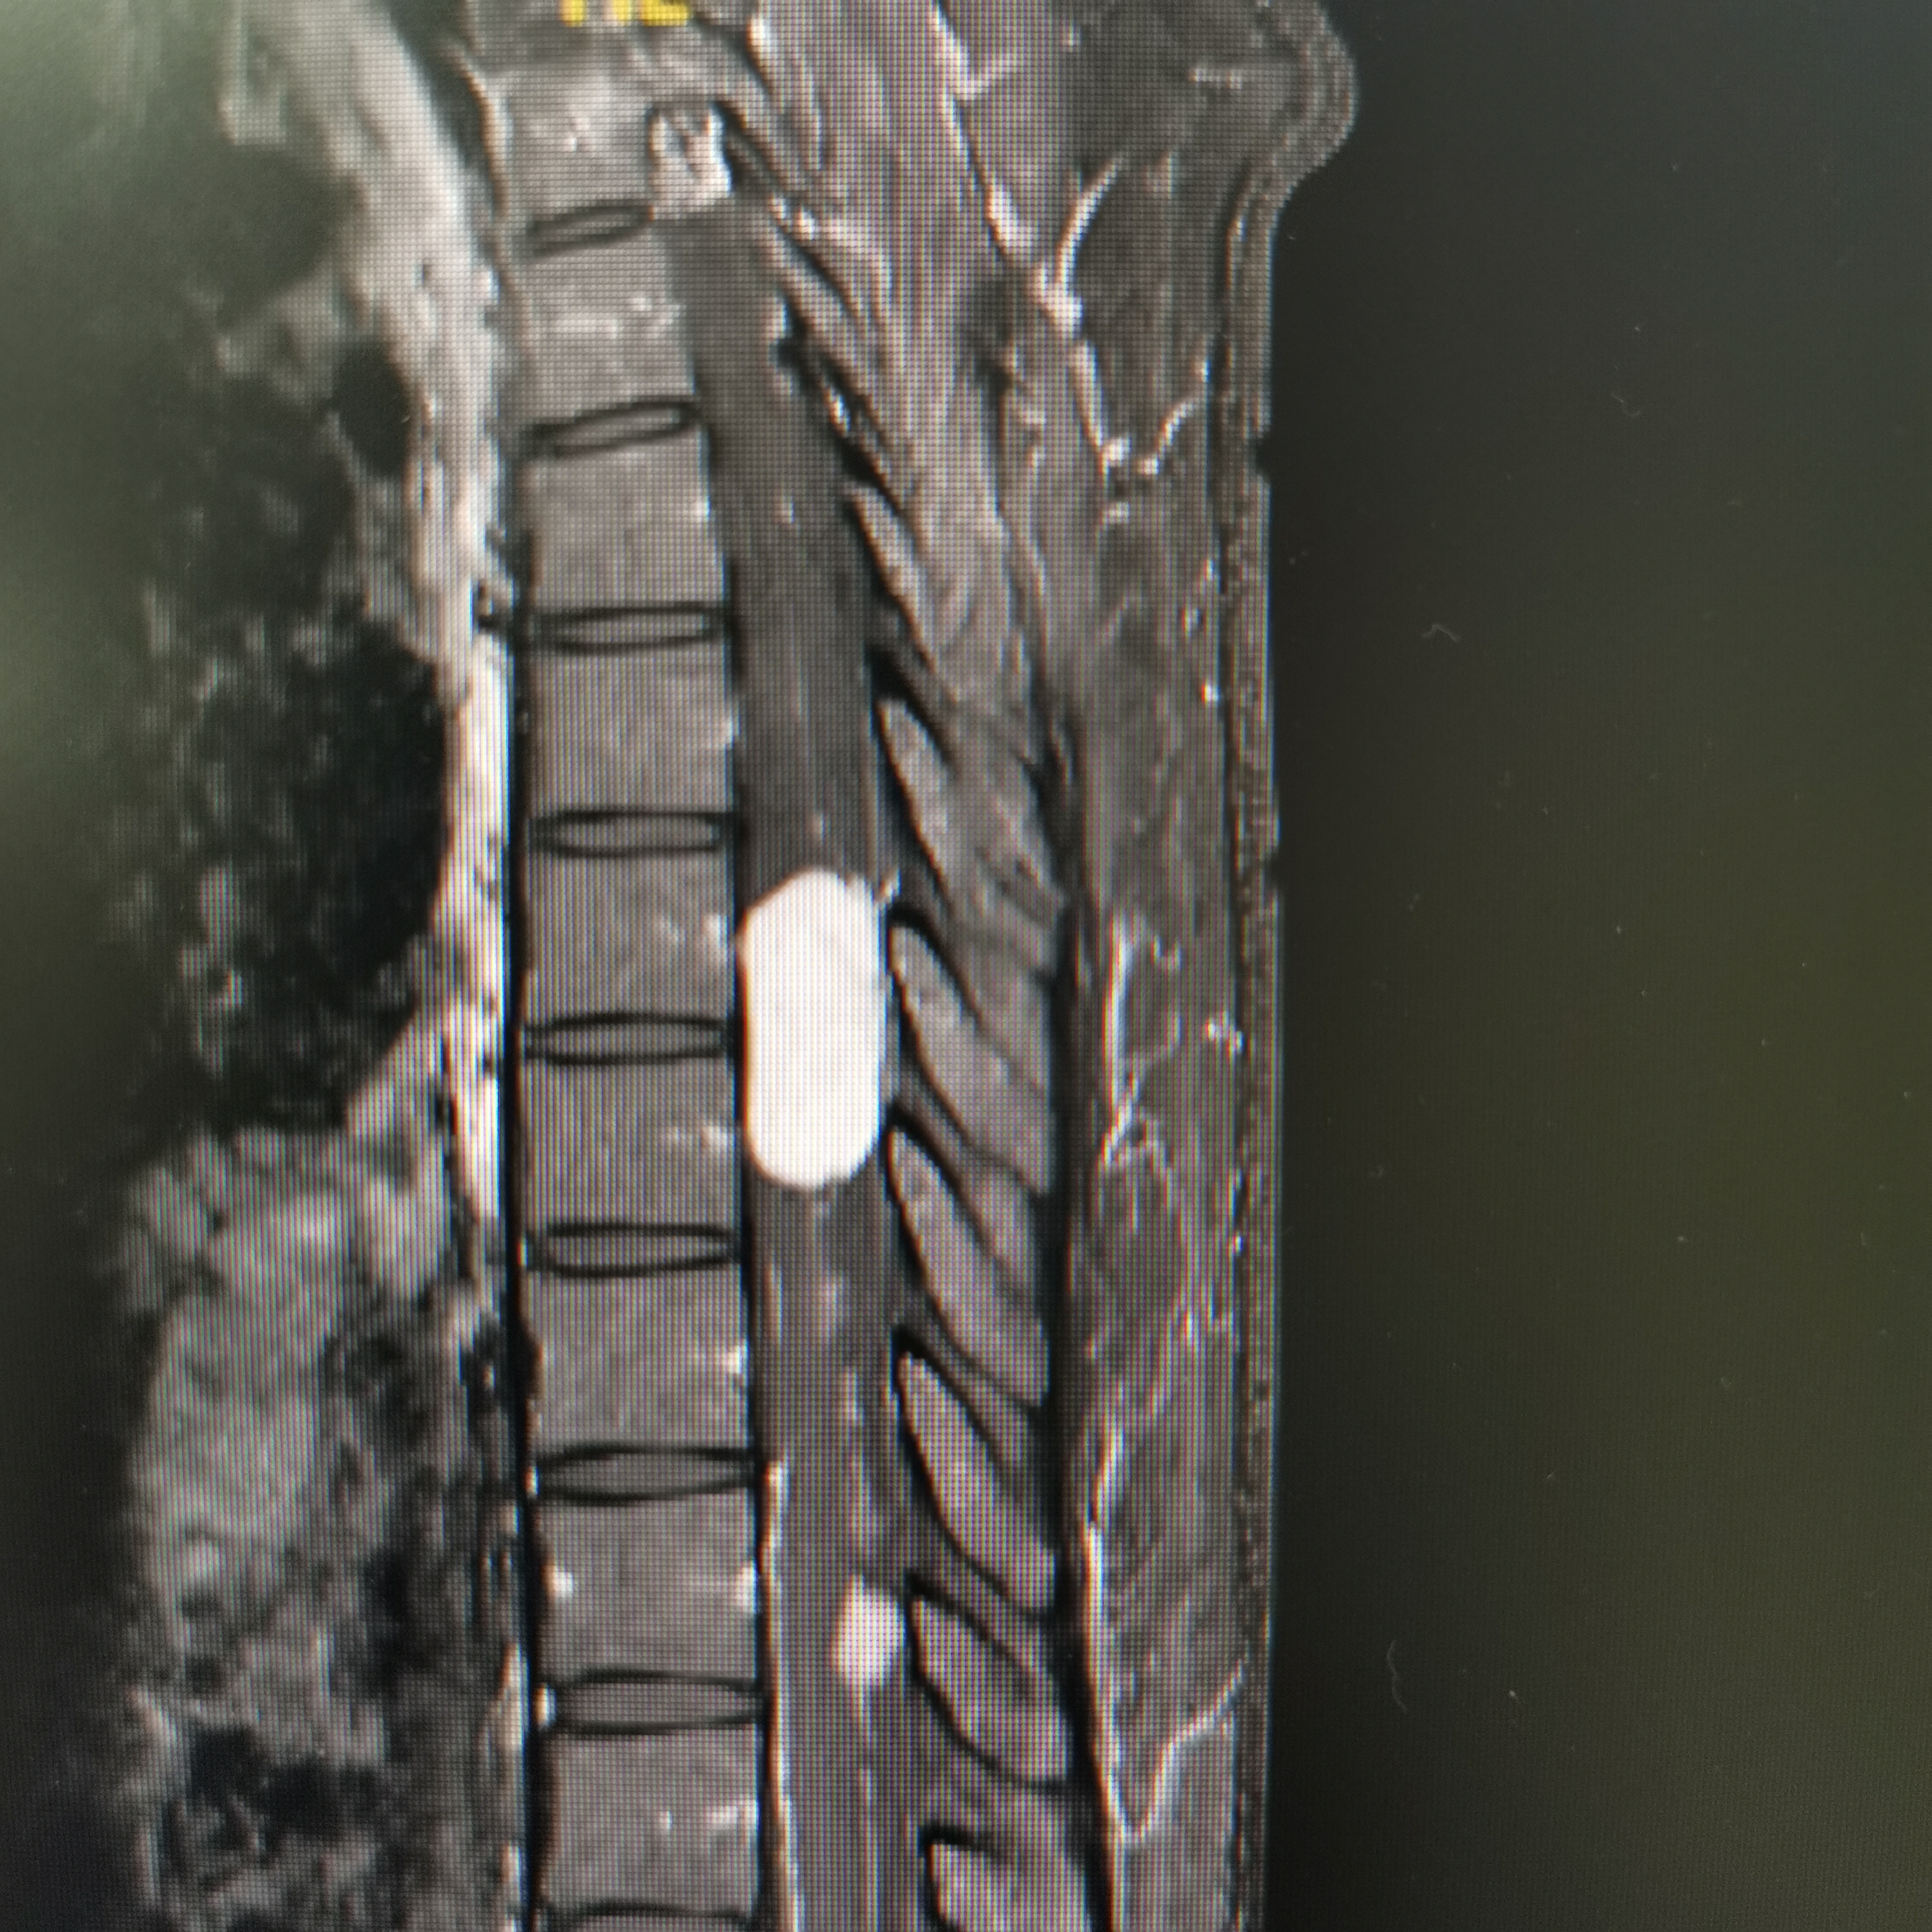

脊髓脊柱-脊髓脊柱肿瘤

神经纤维瘤病的治疗需要综合考虑患者的病情、症状、年龄、身体状况等因素,制定个性化的治疗方案。